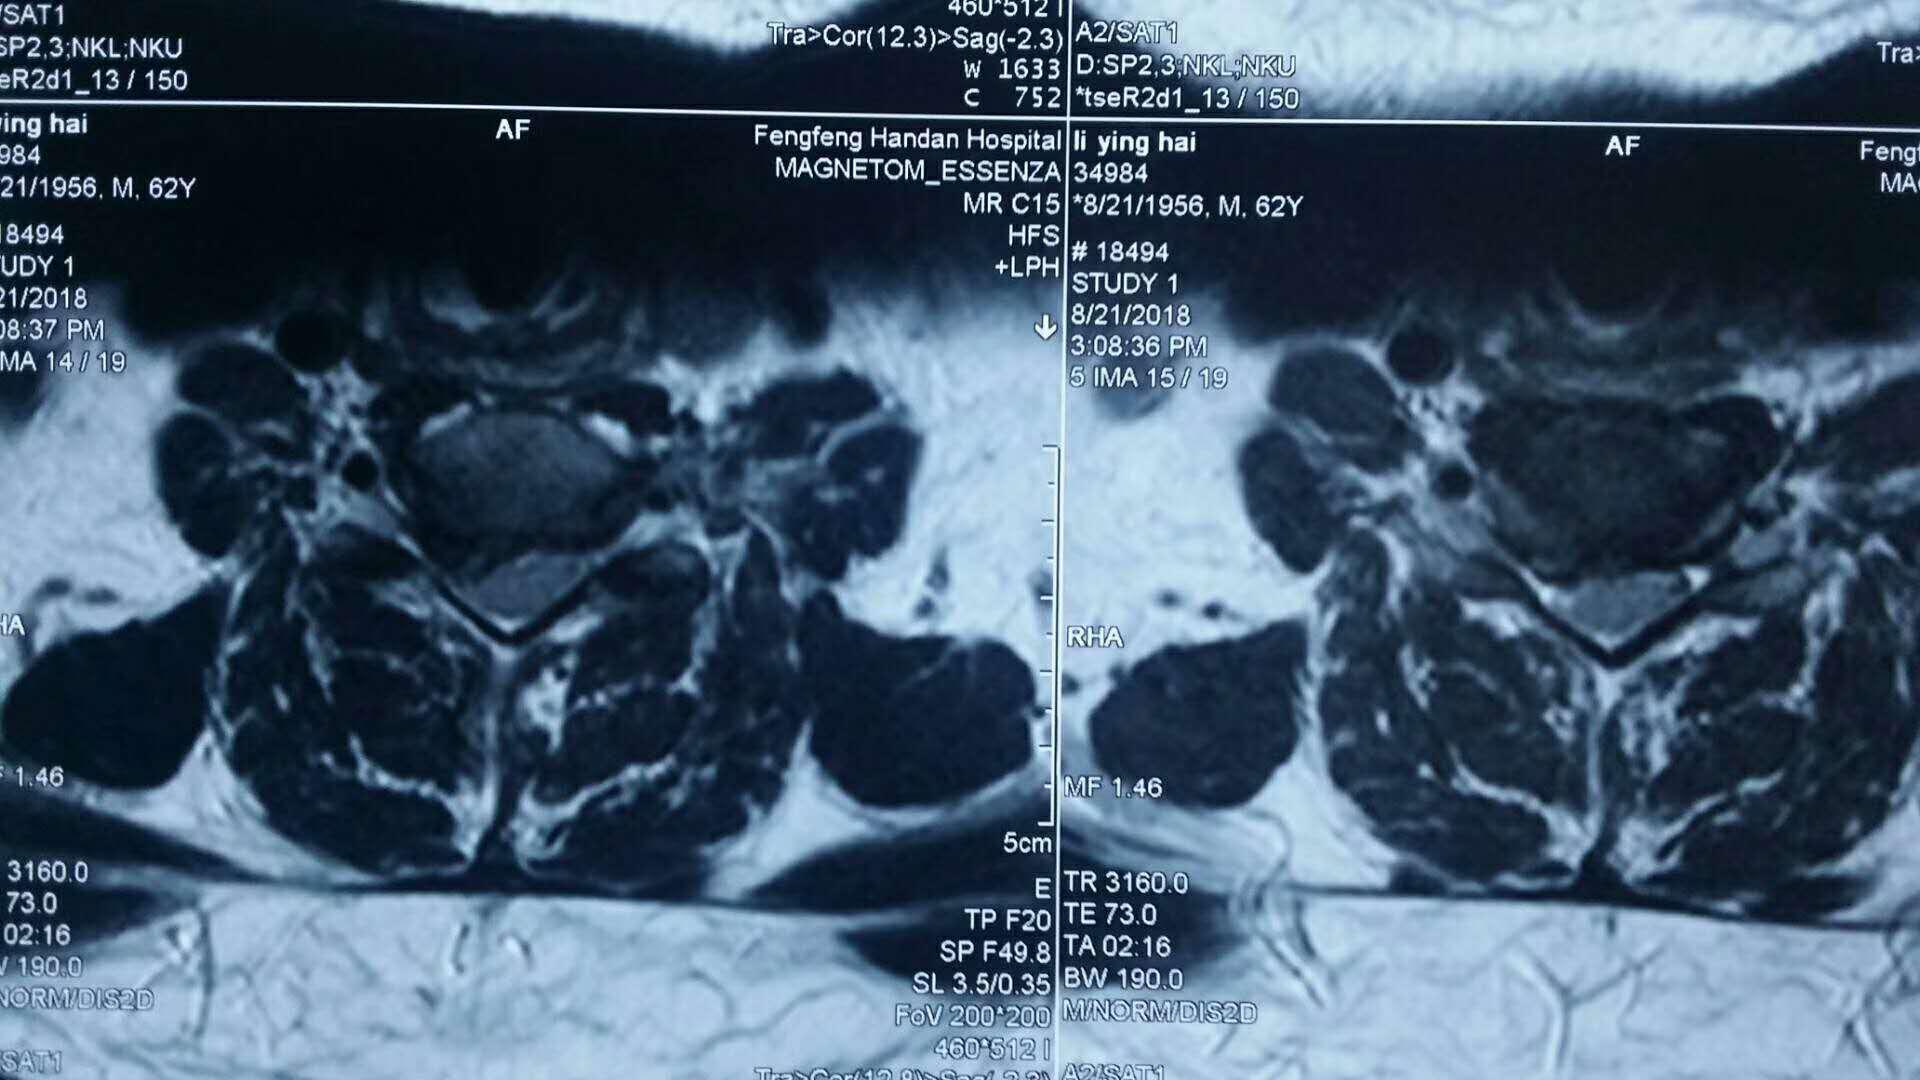

患者颈部MRI图像

此例患者为62岁男性,颈部不适3个月,加重7天伴右上肢疼痛、麻木、无力,不能下垂。经MRI、CT检查显示,颈6、7间盘脱出、游离,利用DeLta技术成功摘除髓核,全麻清醒后症状完全缓解。术后第一天,患者在颈托佩戴保护下行走,对治疗效果表示非常满意,标志着脊柱外科的微创技术又迈上了一个新台阶。